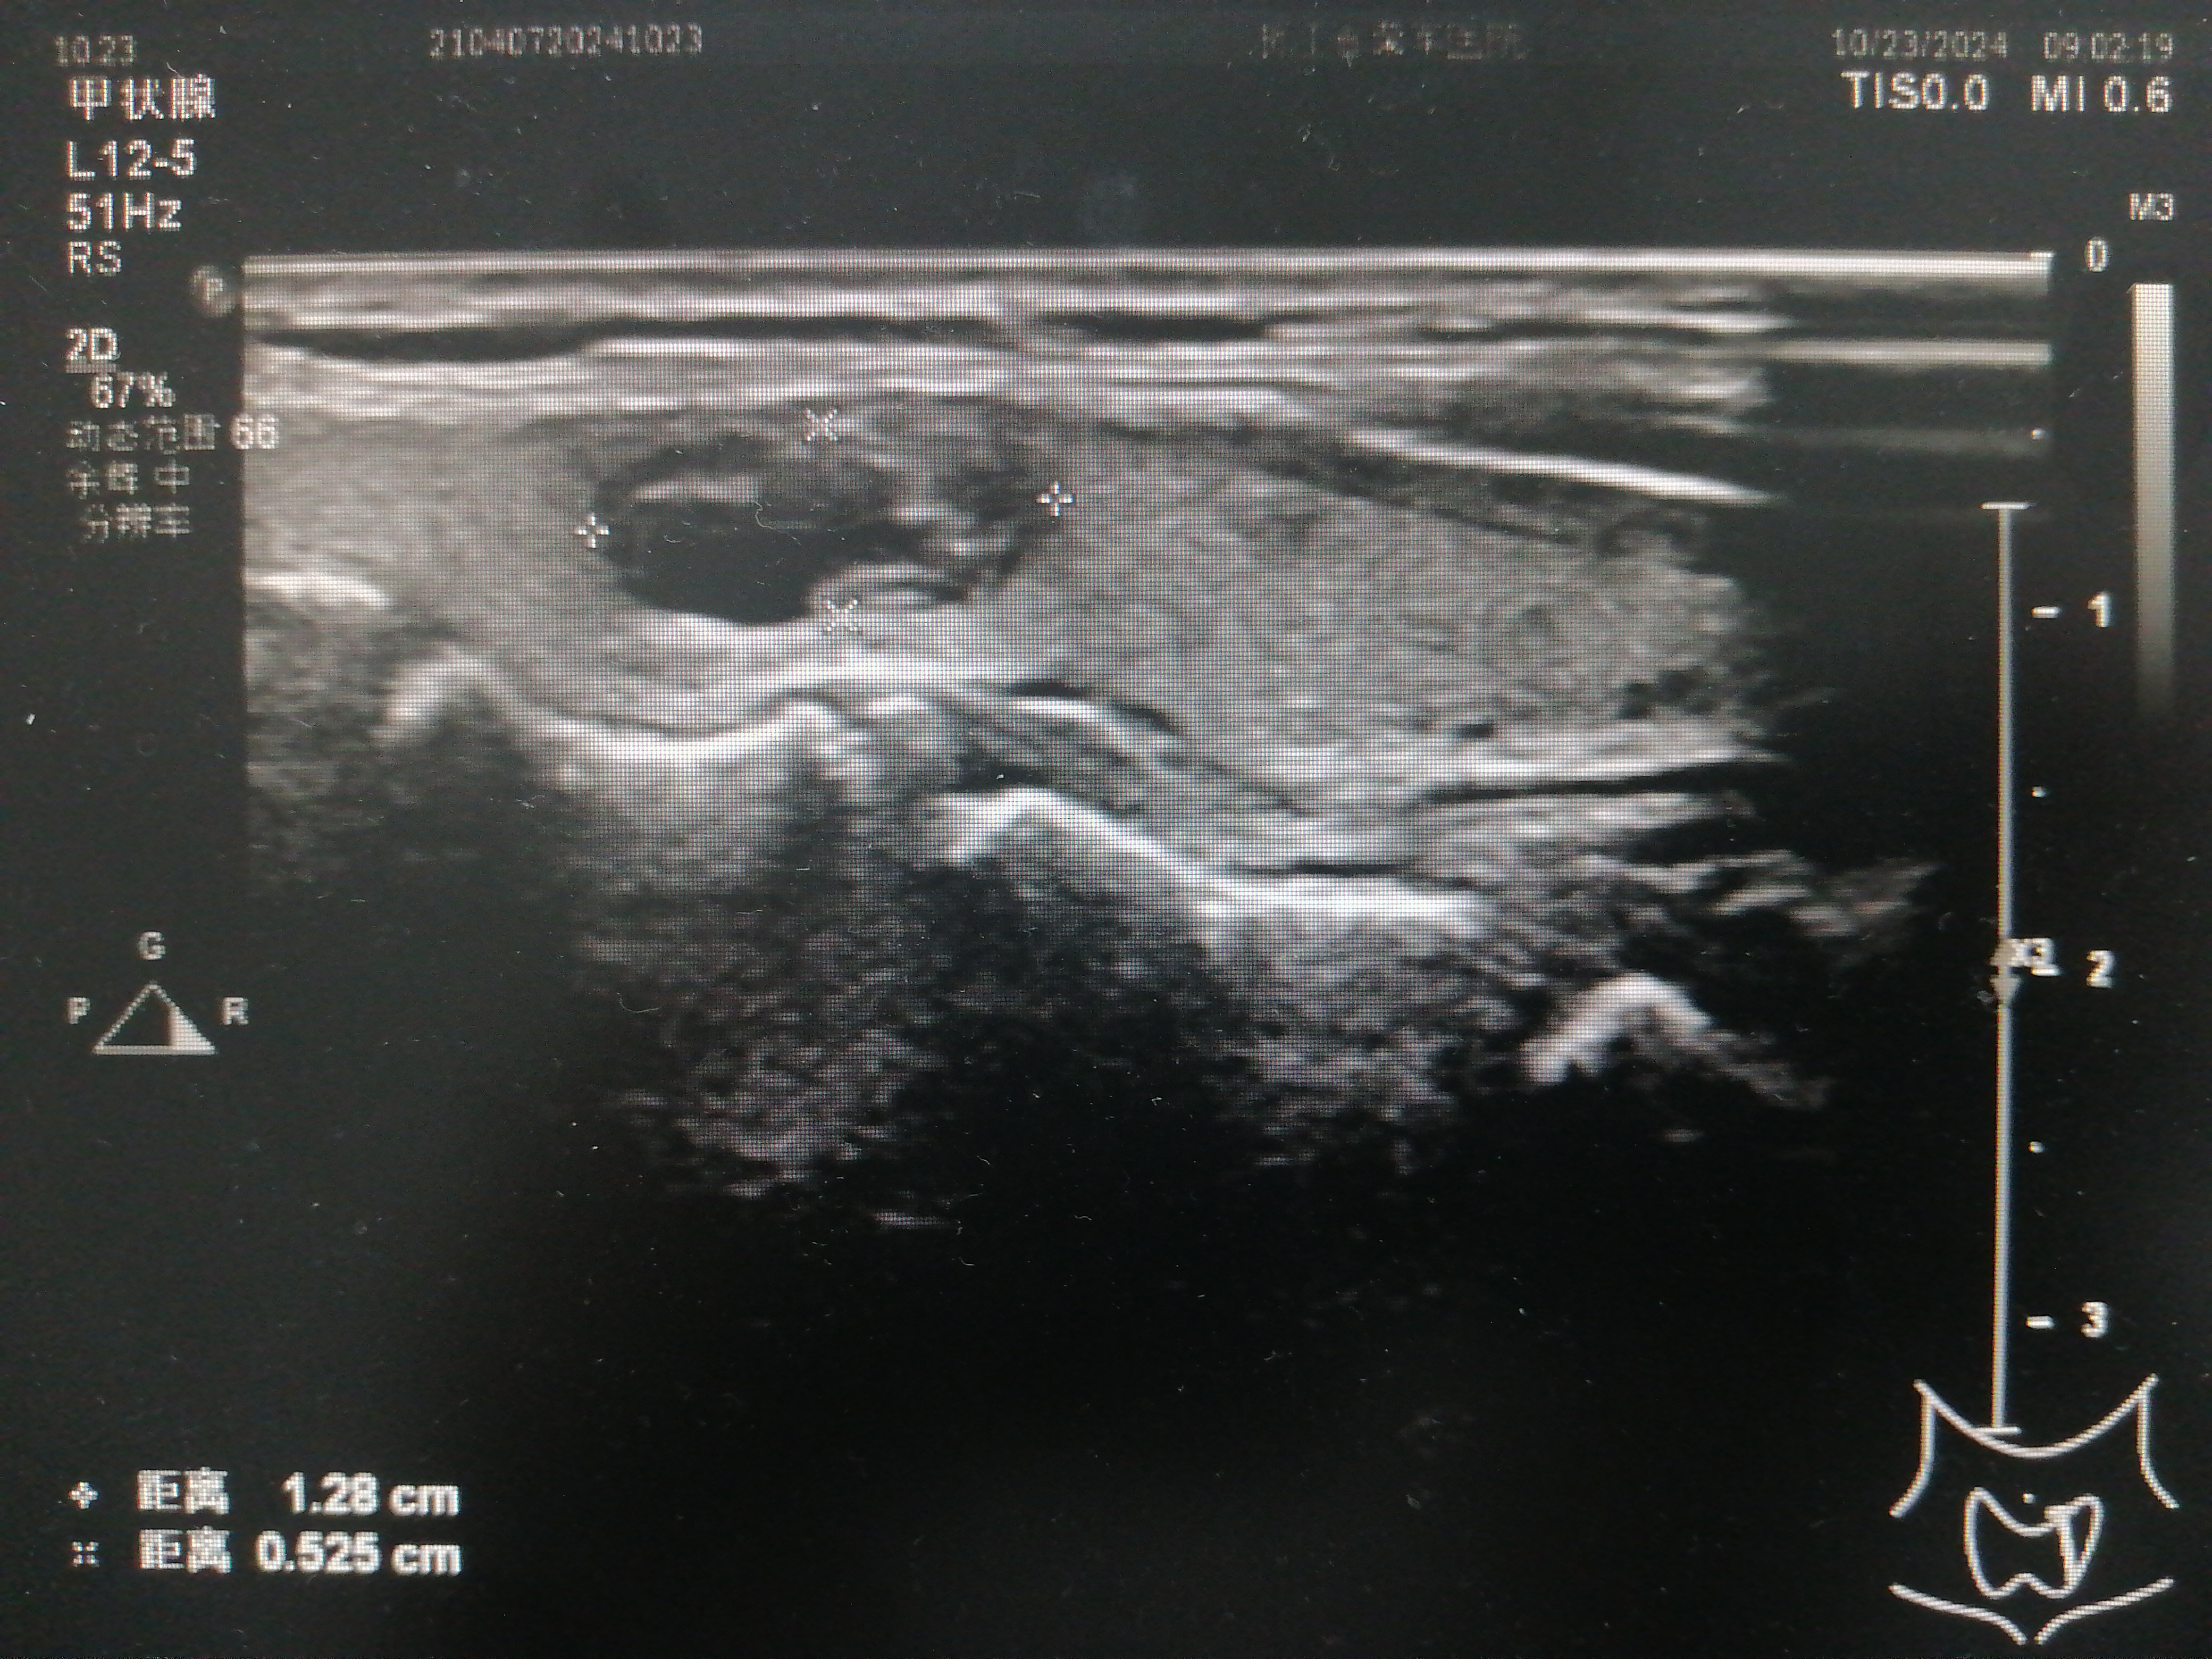

甲状腺结节超声

双侧甲状腺多发结节 c